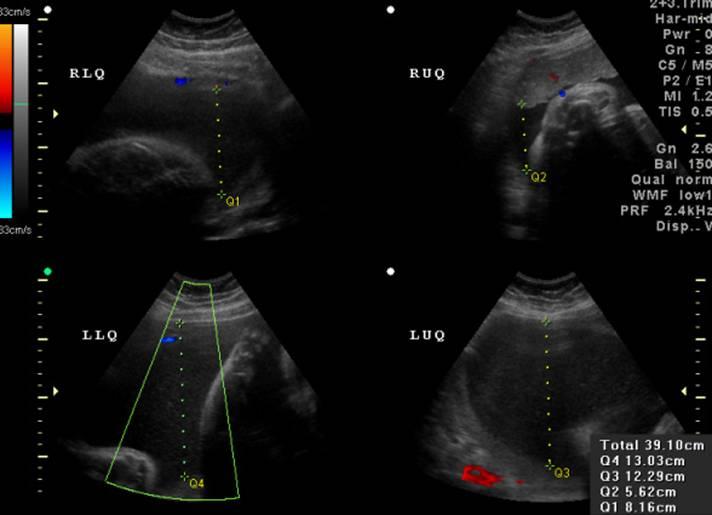

Polyhydramnios is an excess of amniotic fluid with an amniotic fluid index (AFI) >24 cm or deepest vertical pocket >8 cm. It occurs in 1–2% of pregnancies and is associated with impaired fetal swallowing, maternal diabetes, or congenital anomalies. Normal AFI is 8–24 cm. Since the fetus continuously swallows and recycles amniotic fluid, structural gastrointestinal abnormalities such as esophageal atresia can lead to polyhydramnios due to impaired swallowing.

Rationale for correct answers

2. Esophageal atresia prevents the fetus from swallowing and absorbing amniotic fluid. This leads to accumulation, resulting in polyhydramnios, which is a common prenatal ultrasound finding in such cases.

1. Renal agenesis results in oligohydramnios, not polyhydramnios. Absence of fetal kidneys prevents urine production, reducing amniotic fluid volume.

3. Oligohydramnios is the opposite of polyhydramnios, defined as AFI <5 cm or single deepest pocket <2 cm. It is not a condition associated with increased amniotic fluid.

4. Fetal growth restriction may be associated with oligohydramnios due to placental insufficiency, not polyhydramnios.

- Polyhydramnios is defined as AFI >24 cm or deepest vertical pocket >8 cm.

- It is commonly associated with impaired fetal swallowing, such as in esophageal atresia.

- Renal agenesis and growth restriction are linked with oligohydramnios, not polyhydramnios.

- Maternal diabetes is another important cause of polyhydramnios.